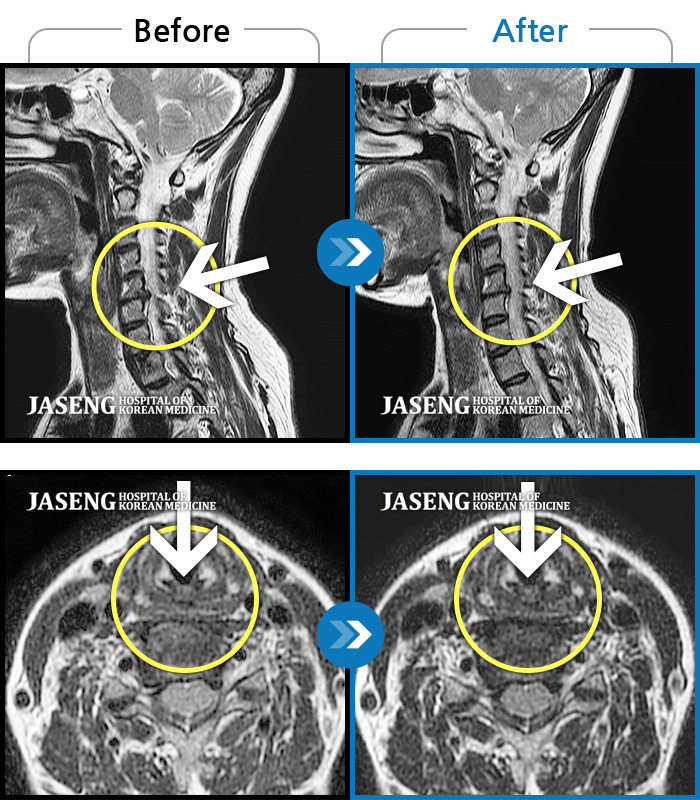

MRI 치료사례

좌측 목 통증 및 견갑내연 통증, 팔 전체 통증으로 일상생활에 어려움을 겪는 상태로 내원하셨습니다.